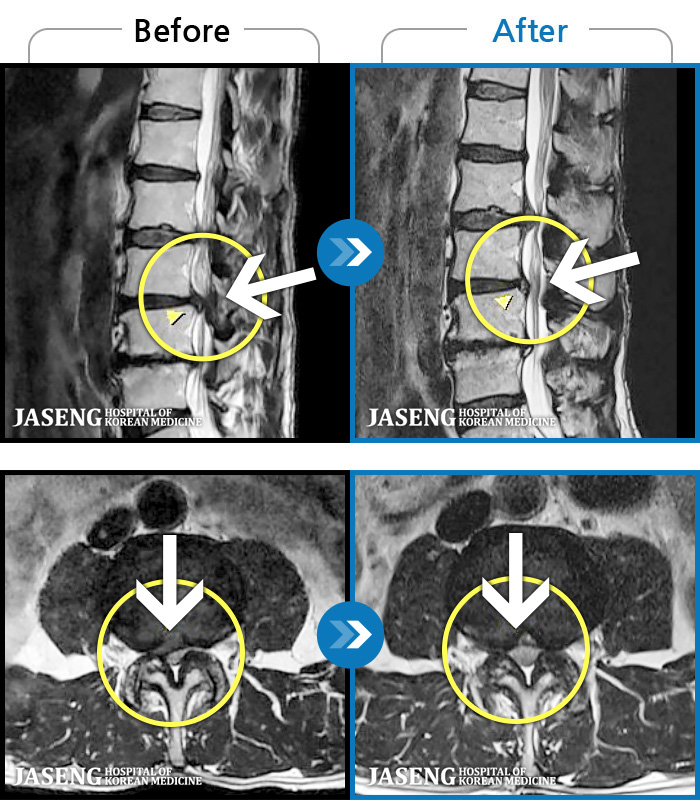

MRI ġ

1,301 MRI ũ ʸ Ȯϼ.